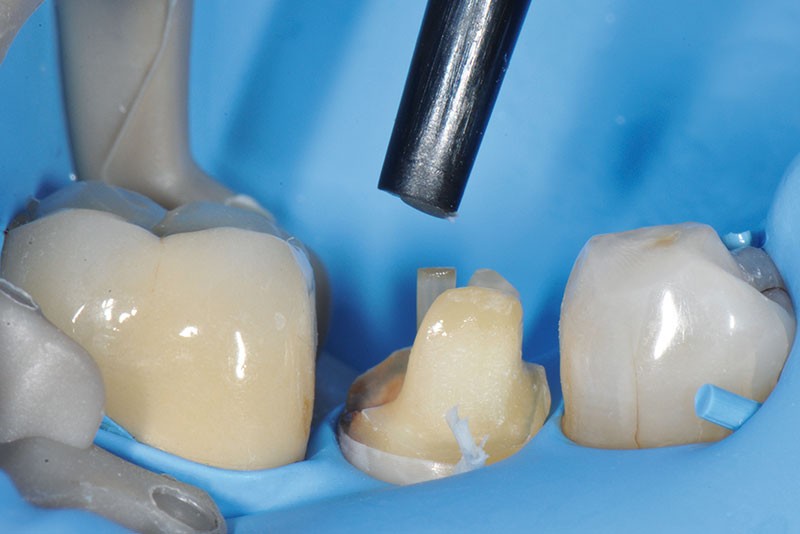

22, 23, 24. Un deuxième incrément de composite est appliqué pour terminer le moignon avant polymérisation finale. La préparation périphérique est terminée.